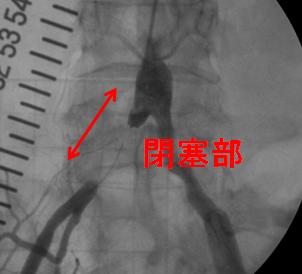

PTA(経皮的血管形成術)

足の血管が狭くなると、しばらく歩くと足が痺れたり、痛みが出現するが、休憩をすると元に戻るという症状が出現します。腎臓の血管が狭くなると血圧上昇や腎機能低下をきたす原因にもなります。経皮的血管形成術とは心臓以外の血管(例えば手足の血管や腎臓の血管など)が動脈硬化により血管内腔が狭くなった所を風船やステント(金属のコイル)を用いて、広げる治療です。足に関しては治療が成功すると痺れたりすることなく歩行が可能となり、腎臓に関しては血圧や腎機能の改善を認めるようになります。